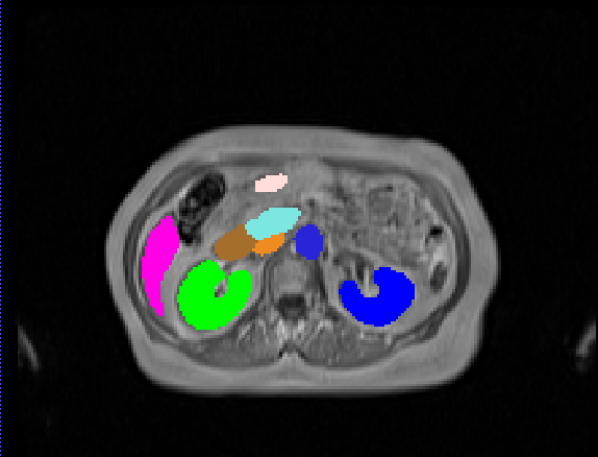

Manual Labels for Verification. We design a mechanism to validate these collected labels by humans. To do so we collect manual labels from 3000 2D image from 300 MRI samples for 10 abdominal organs (UKBOB-manual). These manual labels (see examples in Figure 2) act as a validation for the large UKBOB dataset. On these labels, the UKBOB automatic labels obtain an average Dice Score of 0.891 (see Table 3). Furthermore, we verify the spine labels of UKBOB using previously collected manual labels of 200 3D spine labels [5]. We show an example in Figure 1 and we see how the new collected labels match the manual labels in the spine with a total Dice score of 0.811, indicating accurate labels. We discuss in Section 5.1 another mechanism for verifying the labels by zero-shot generalization of trained models to other similar datasets that has manual labels.